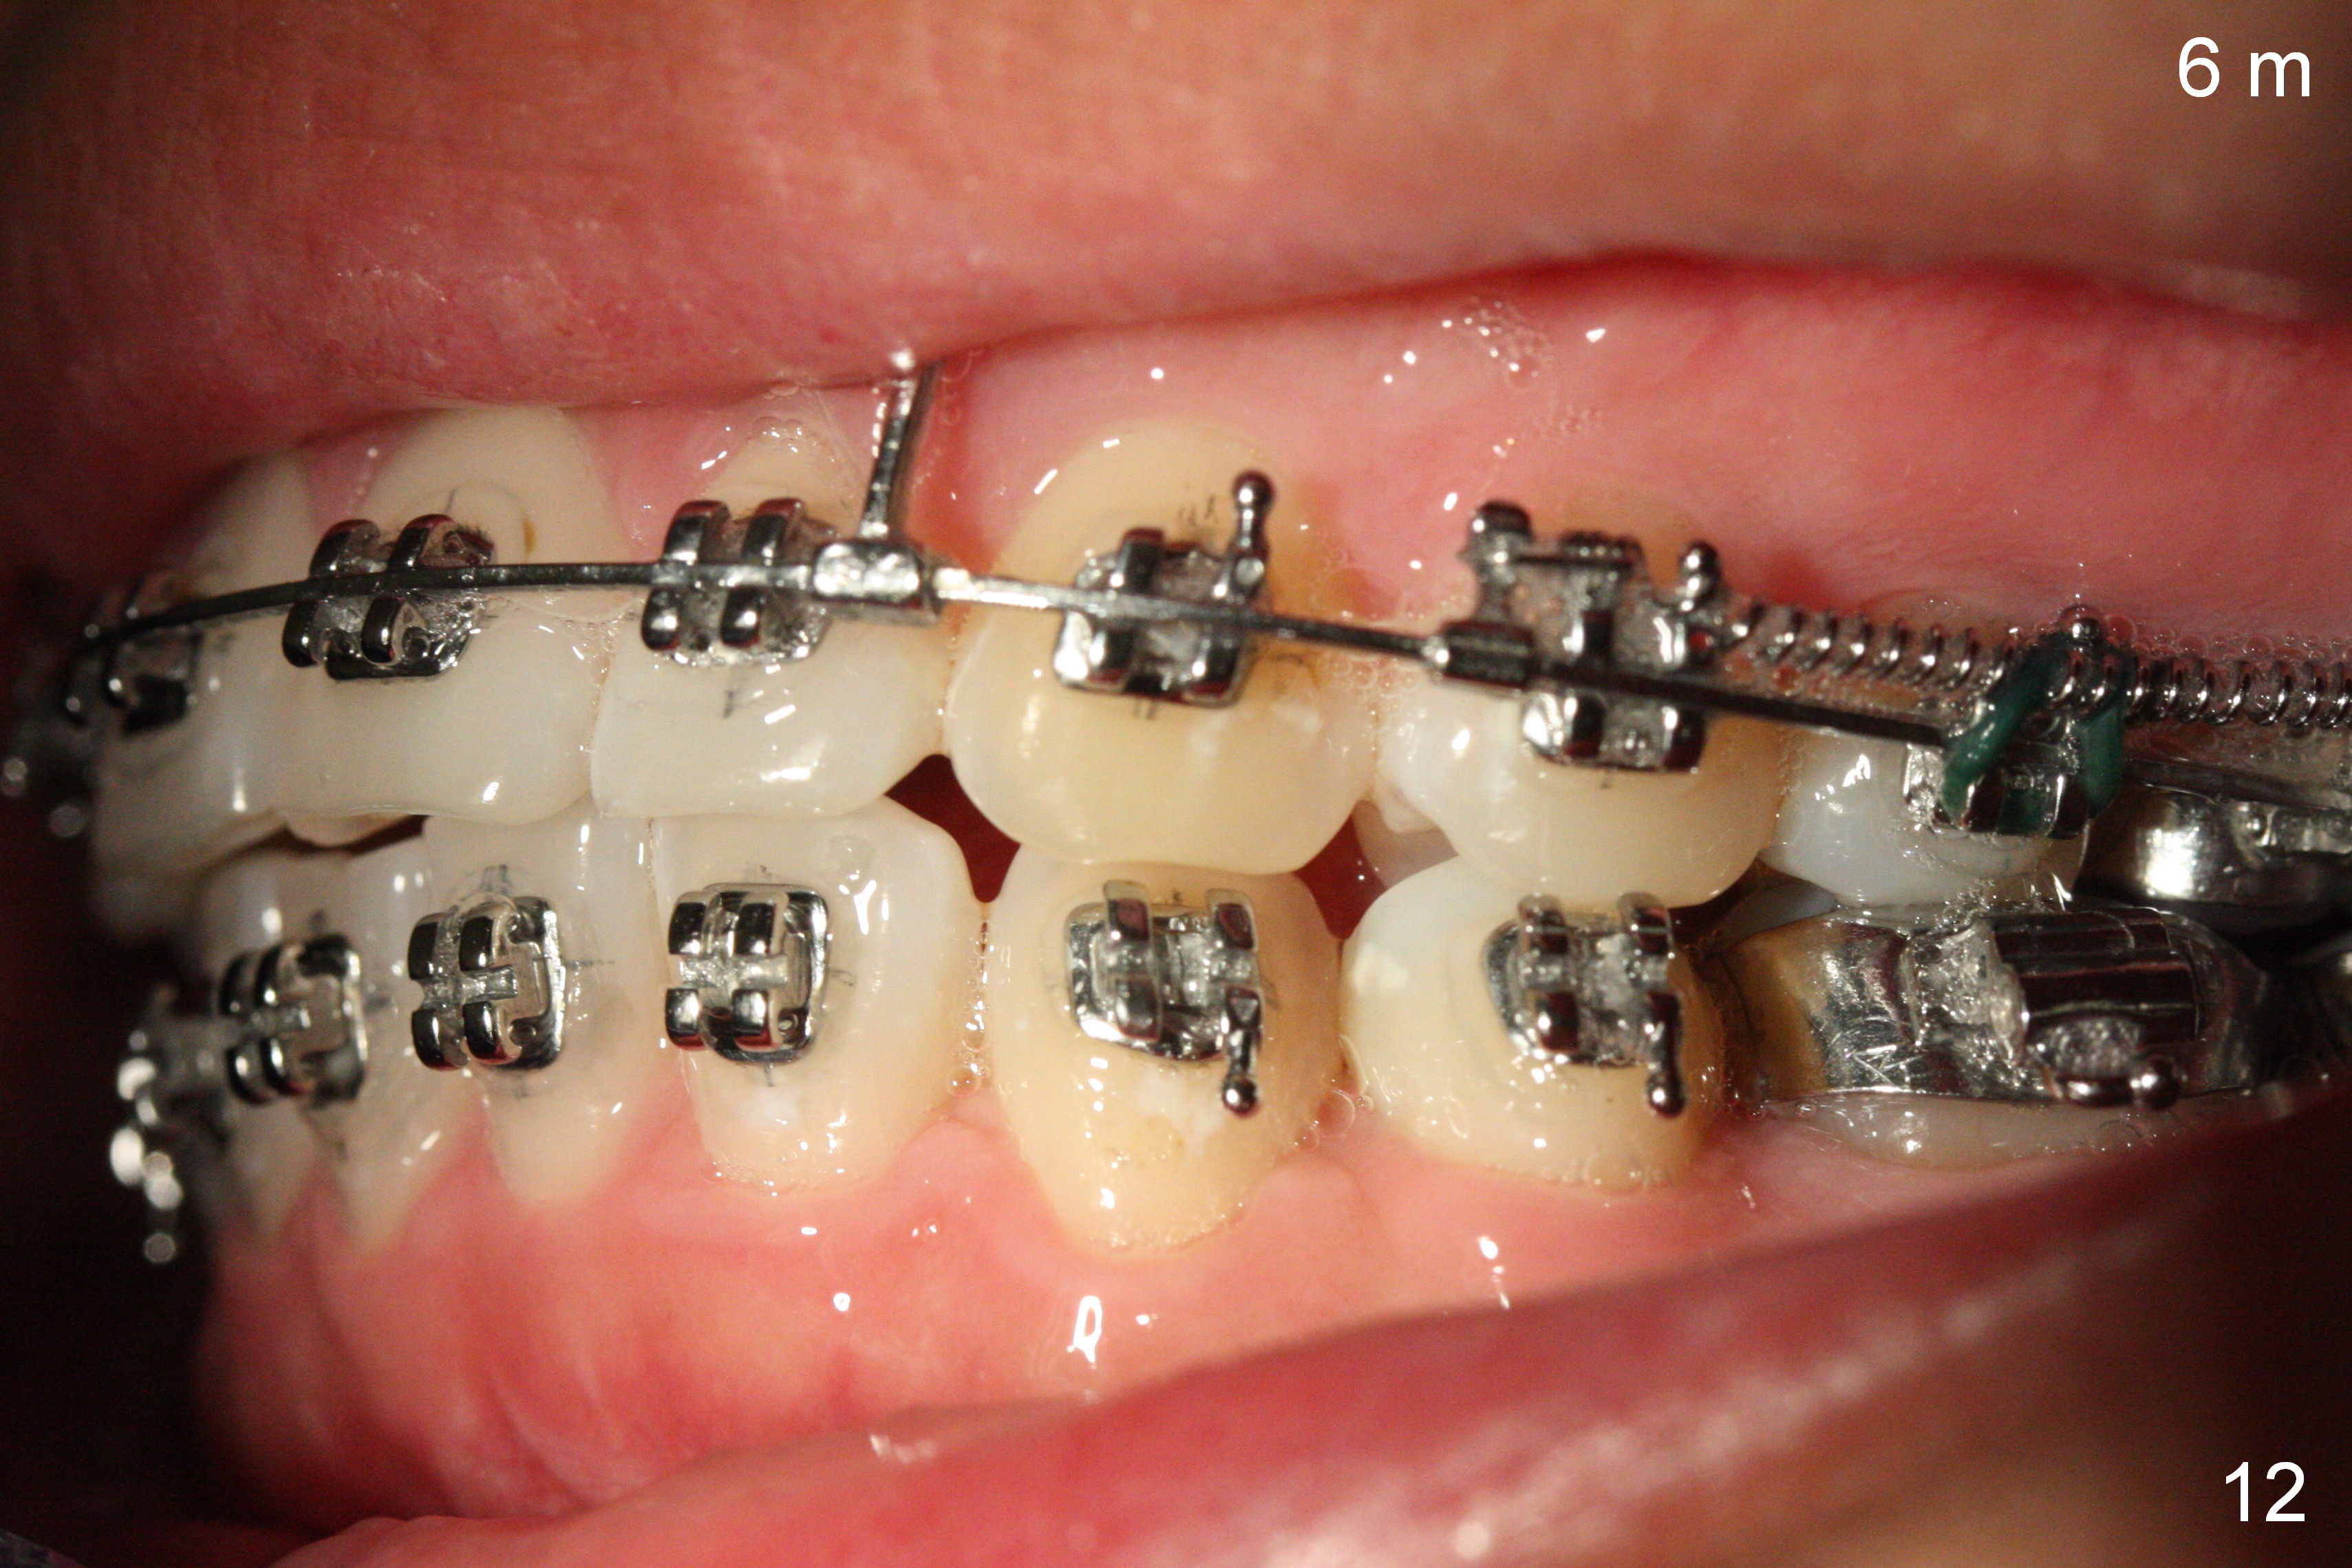

Postop follow up at 1 week (Fig.5,6), 2 months (Fig.7,8) and 3 months (Fig.9,10).  Granulation tissue forms around the entrance of closed coil spring with tenderness 2 months postop (Fig.7,8).  Pain persists especially on the left.  Tension of coiled spring associated with zygomatic implants is low; new coiled springs are added for the posterior implants (Fig.9,10).  Later the left spring associated with the left zygomatic implant fractures.

Six months post zygomatic implants, the profile, anterior overbite and overjet and the right posterior interdigitation are within normal limit (Fig.11), whereas the left one not (Fig.12).  The lower midline appears to be deviated to the left.  Elastics are used for correction (Fig.11,13,14).  A second option is to reduce the number of closed springs on the right and increase the one on the left.